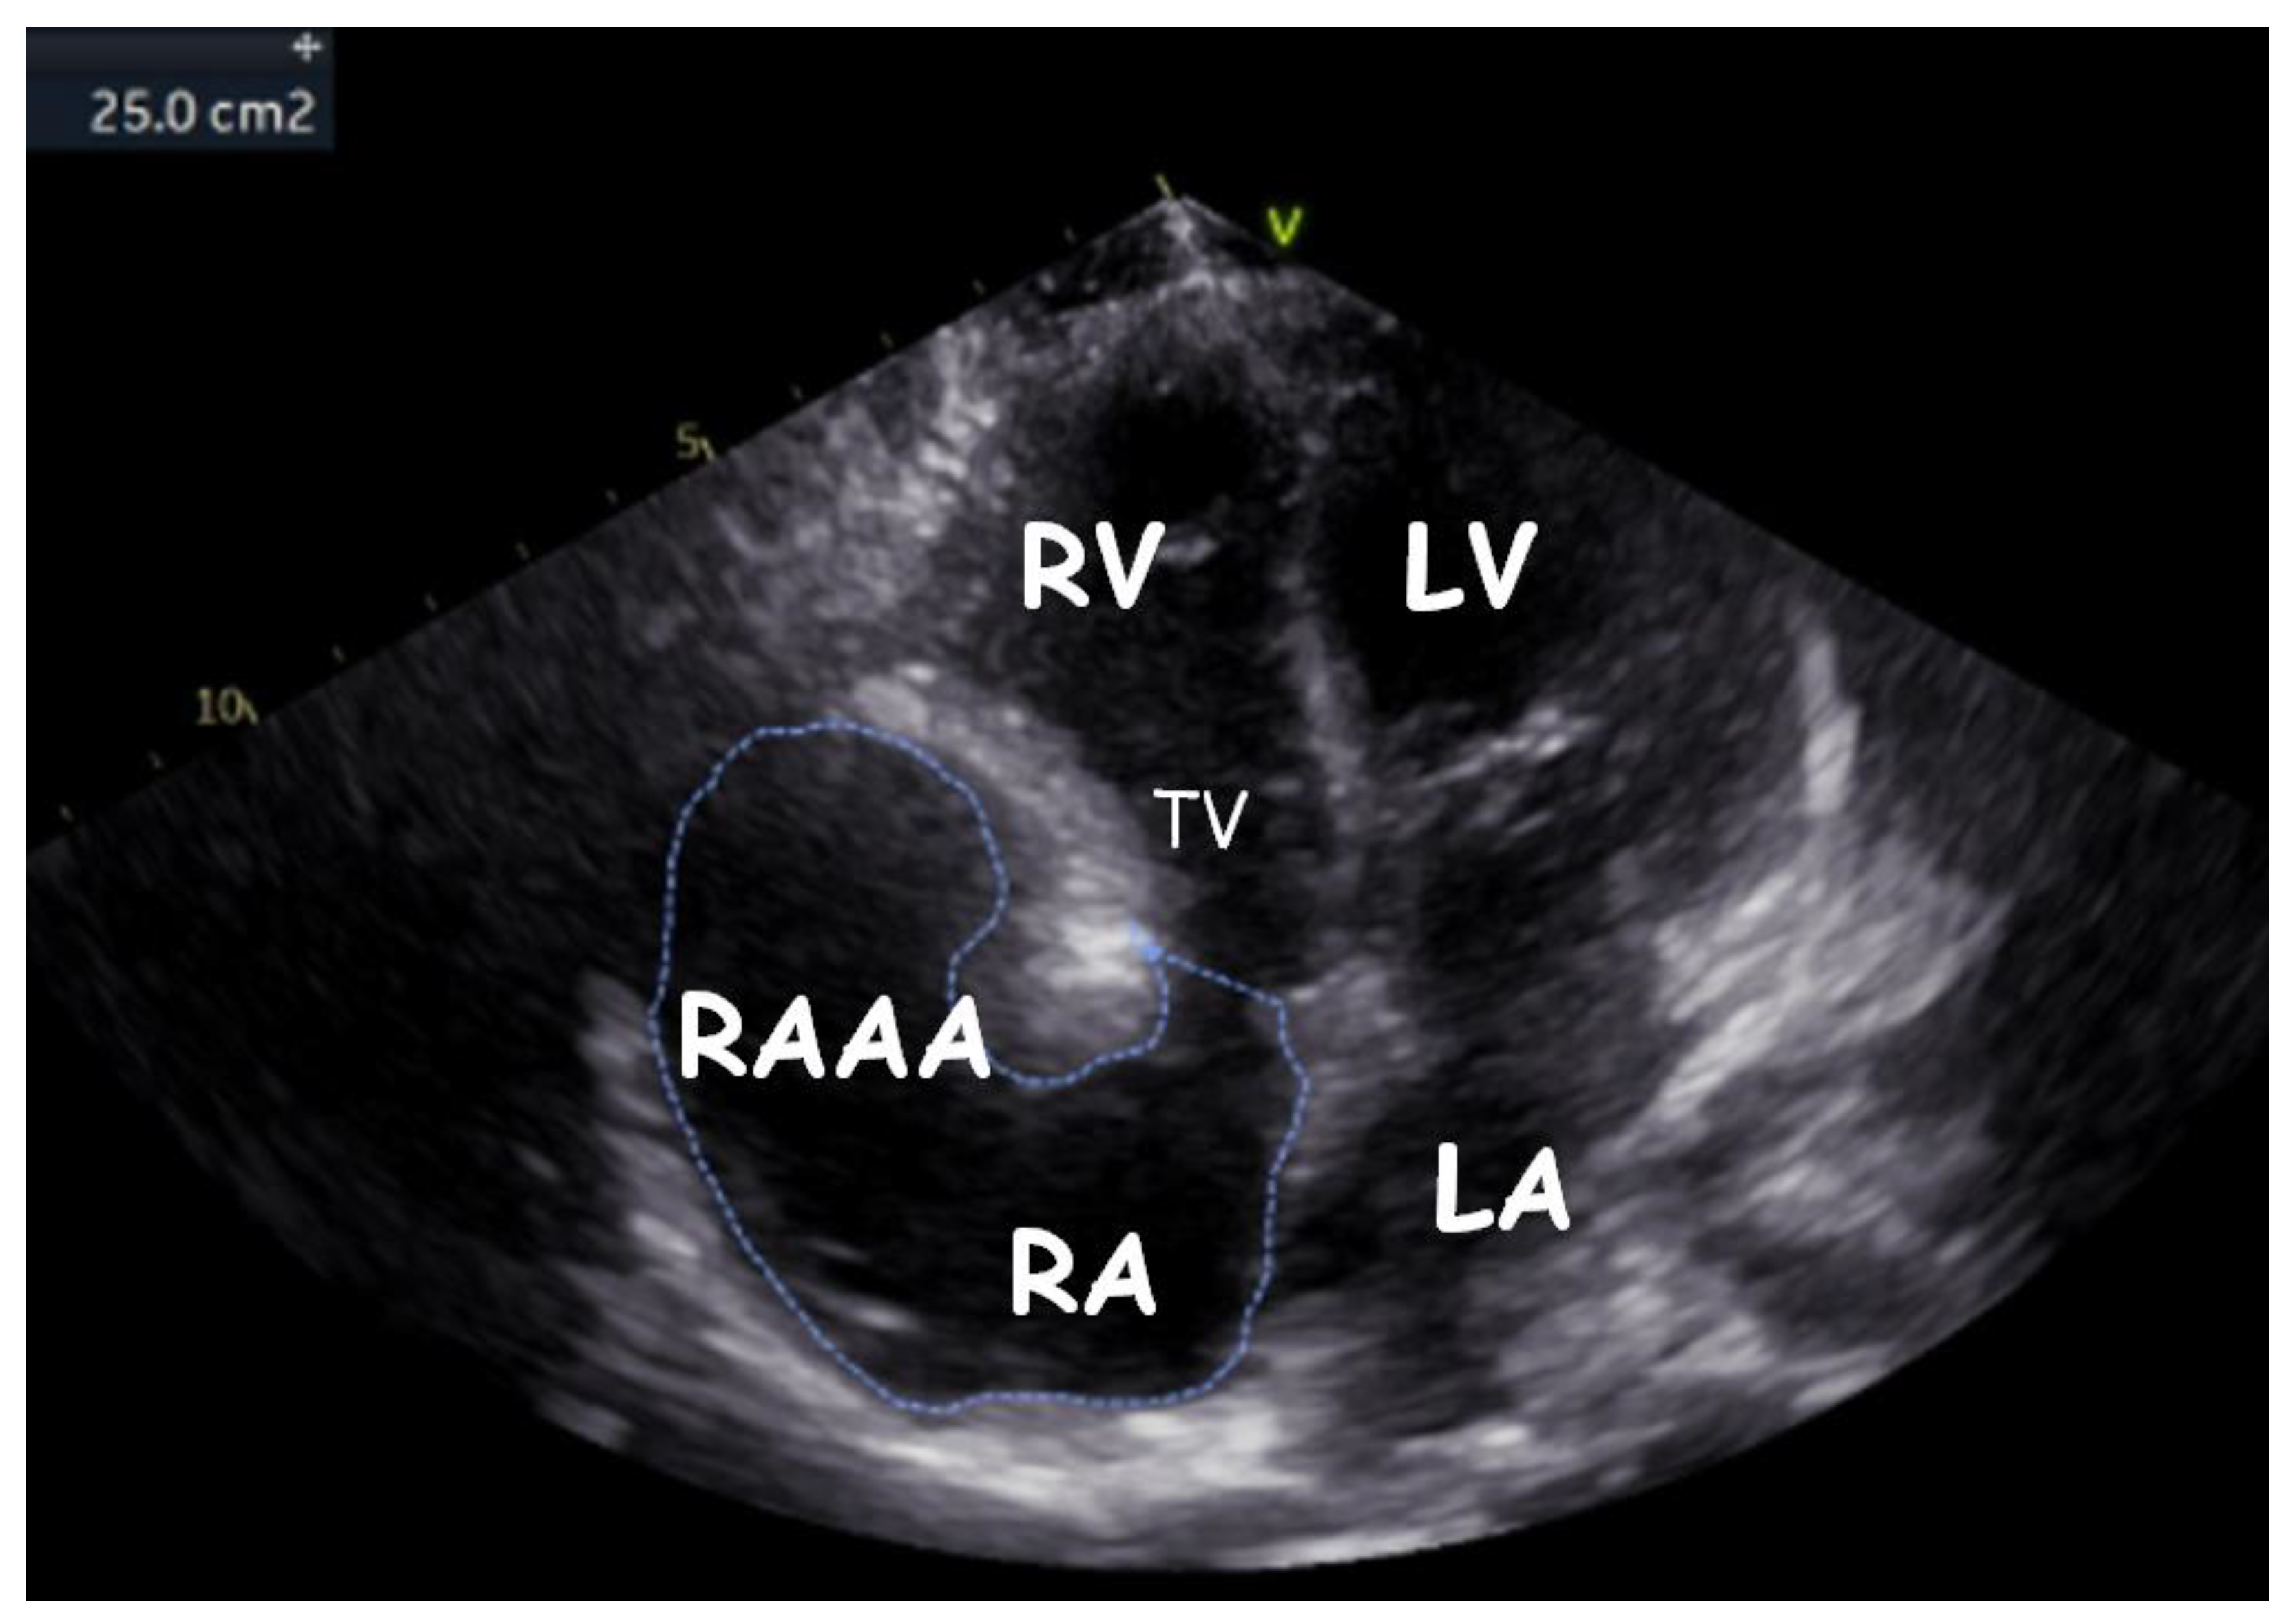

| RAAA | Right Atrial Appendage Aneurysm |

| RAA | Right Atrial Appendage |

| RV | Right Ventricle |

| RA | Right Atrium |

| LV | Left Ventricle |

| LA | Left Atrium |

| TV | Tricuspid Valve |